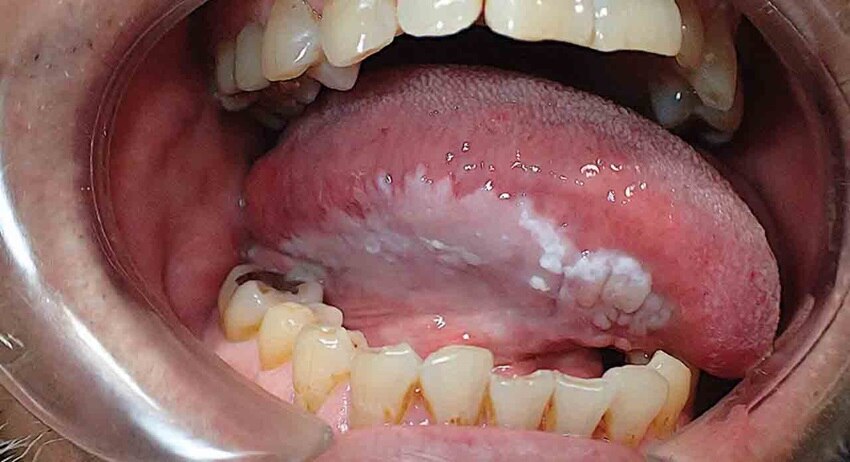

• Bạch sản lông miệng (Oral hairy leukoplakia): Dạng bạch sản này thường do nhiễm HIV/AIDS hoặc virus Epstein-Barr gây ra và tiến triển thành ung thư miệng. Các mảng lông màu trắng, thường xuất hiện ở các nếp gấp trên lưỡi hoặc những khu vực khác trong miệng.

Bệnh bạch sản lông miệng (Oral hairy leukoplakia)

• Bạch sản dạng lông thường xuất hiện mảng lông trắng mờ dạng nếp gấp.